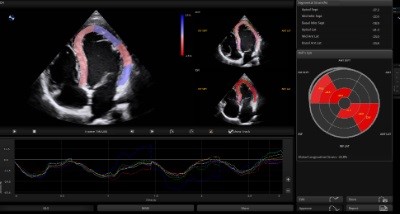

Auto SG

Global and regional myocardial function can be evaluated by Auto SG, an automatic quantitative assessment tool.